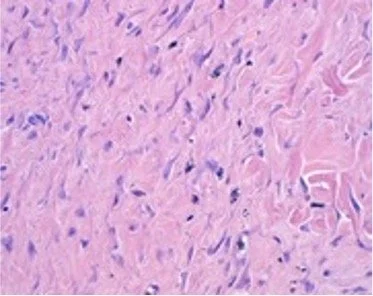

Healthy dermal tissue observed six months post-treatment

High magnification histology results

Treated tissue show nearly 100% elimination of tattoo ink